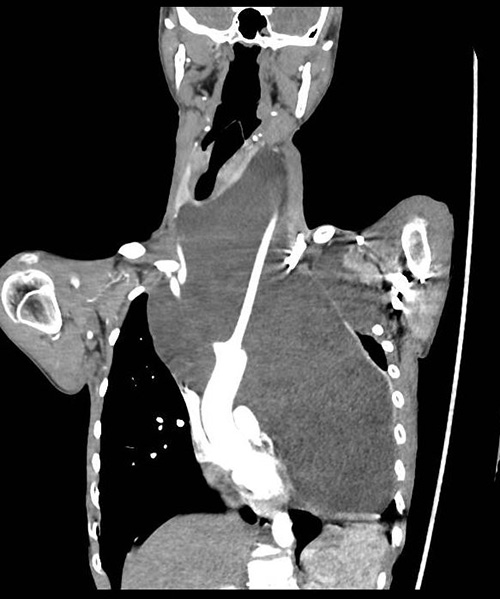

患儿小宇(化名)曾因脂肪母细胞瘤在外院分别接受过颈部、胸部手术。近期,肿瘤再次复发并迅猛增长,巨大的瘤体跨越颈部、胸腔,心脏、气管严重受压,导致他无法平卧入睡,呼吸与循环系统承受着巨大压力。

由于小宇的气管被颈纵隔肿瘤挤压推挤严重变形,麻醉插管成为手术的第一道难关。影像中心副主任医师王蓓经CT图像准确测量变形气管的长度及最窄部位直径,为麻醉医生选择气管插管的型号提供重要依据。由于气道受压严重,正常气管插管无法通过气道最窄位置,麻醉科副主任(主持工作)王芳、副主任李立晶团队为小宇申请特制的气管插管,并成功实施麻醉,手术顺利开始。